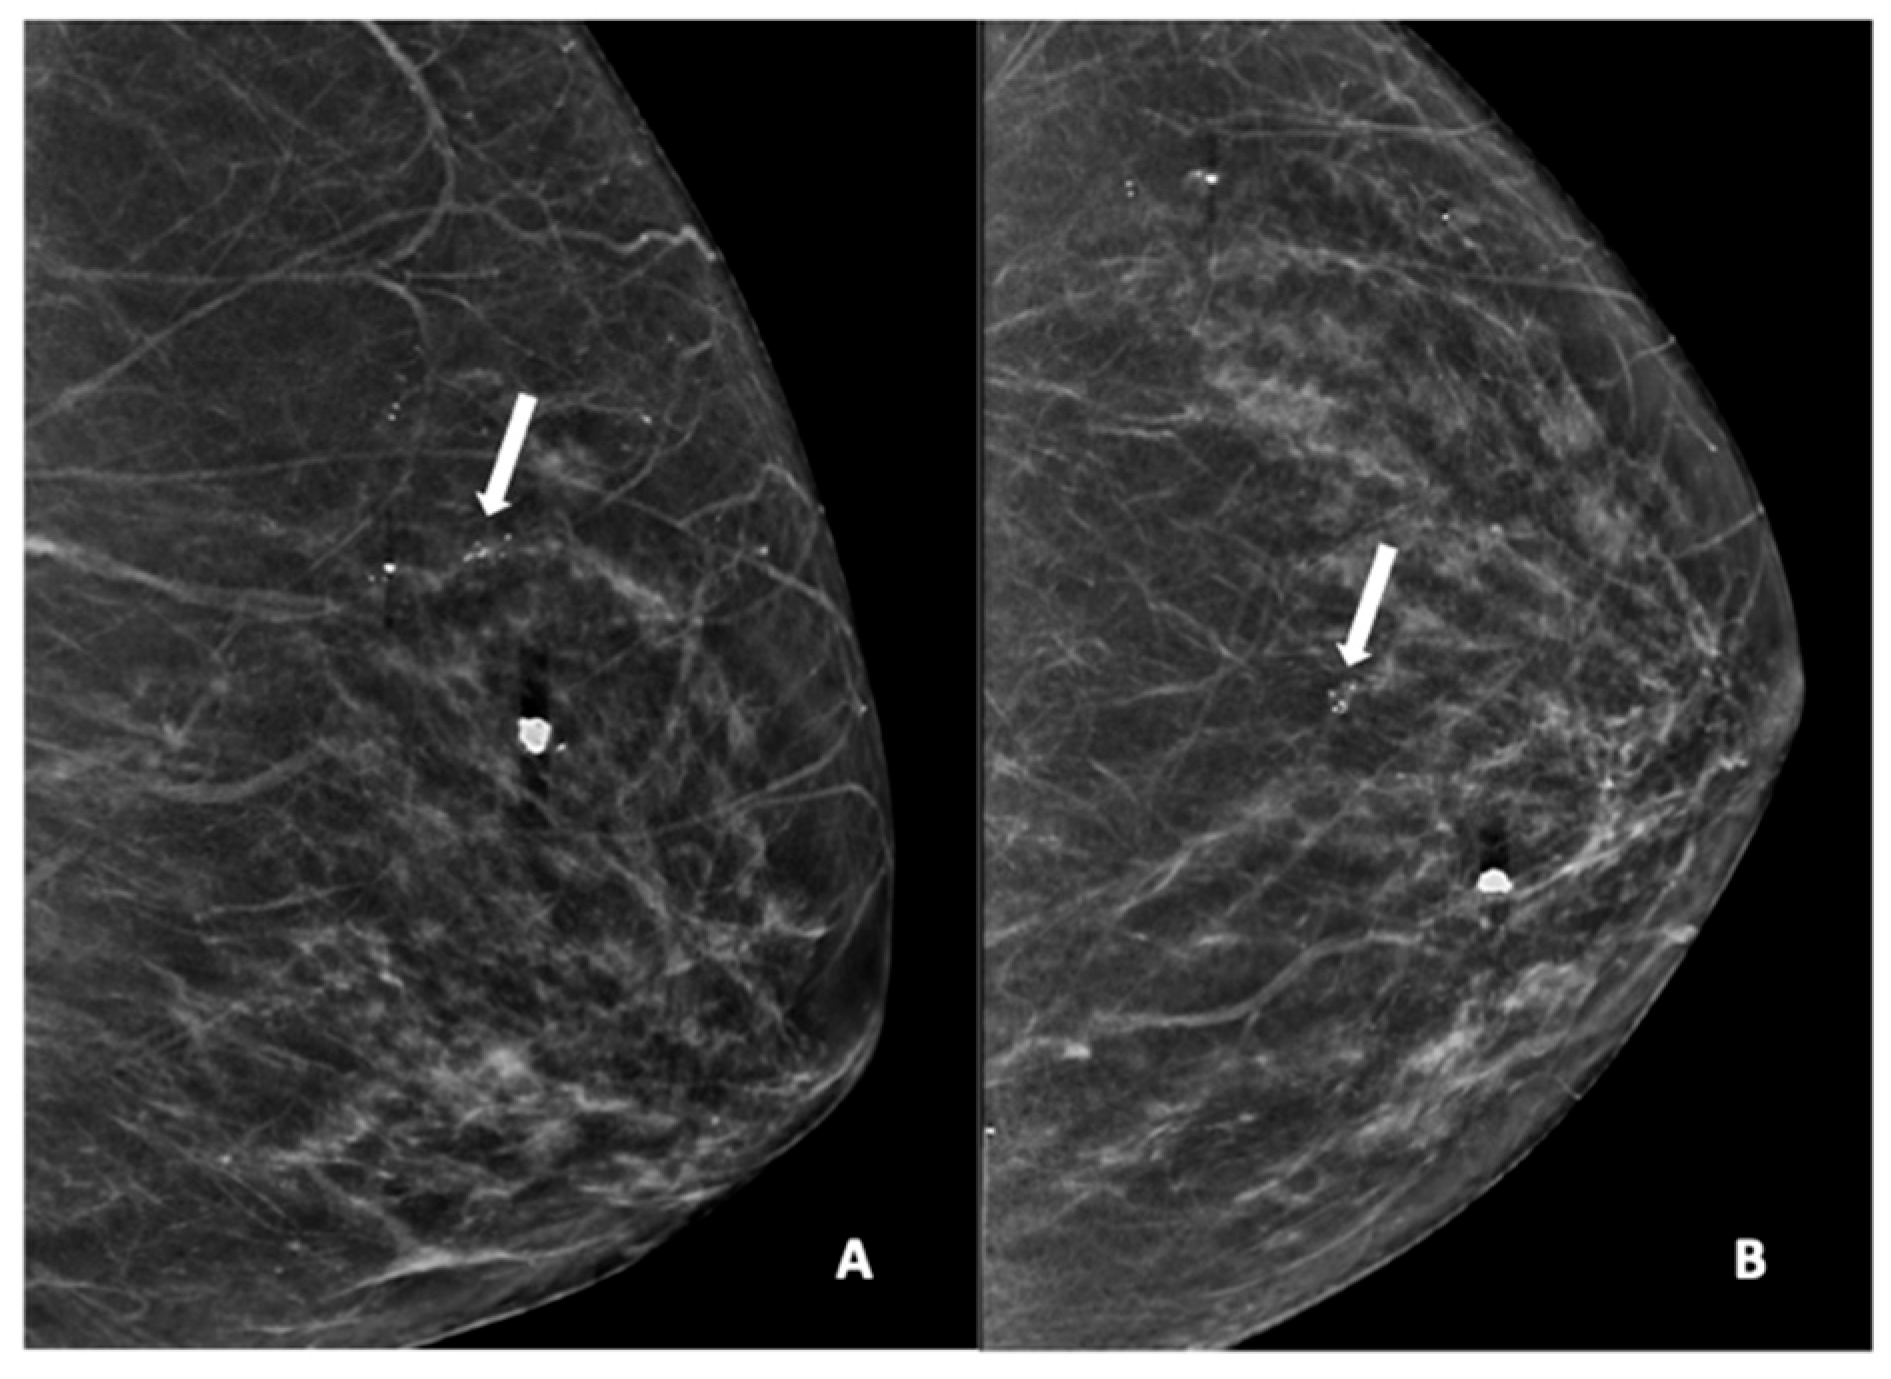

Figure 3.

Mammogram study of a left breast in (A) MLO view and (B) CC view, showing a group of pleomorphic calcifications in the upper mid-quadrant (arrow), reported as BI-RADS 4 lesion. These calcifications were HPE-proven DCIS. There were also benign coarse calcifications in the upper inner quadrant.